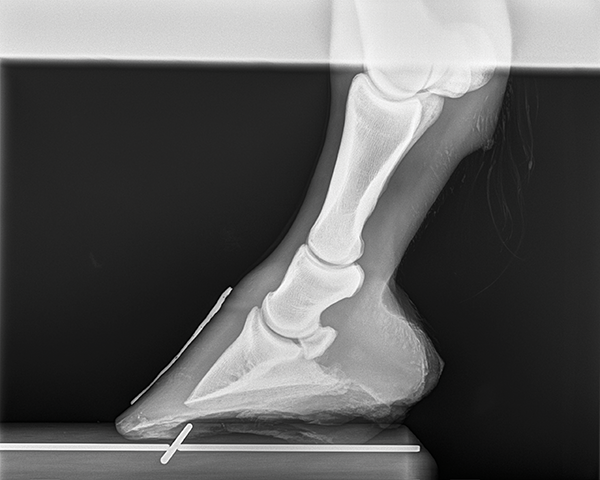

lateral coffin bone projection

lateral navicular projection